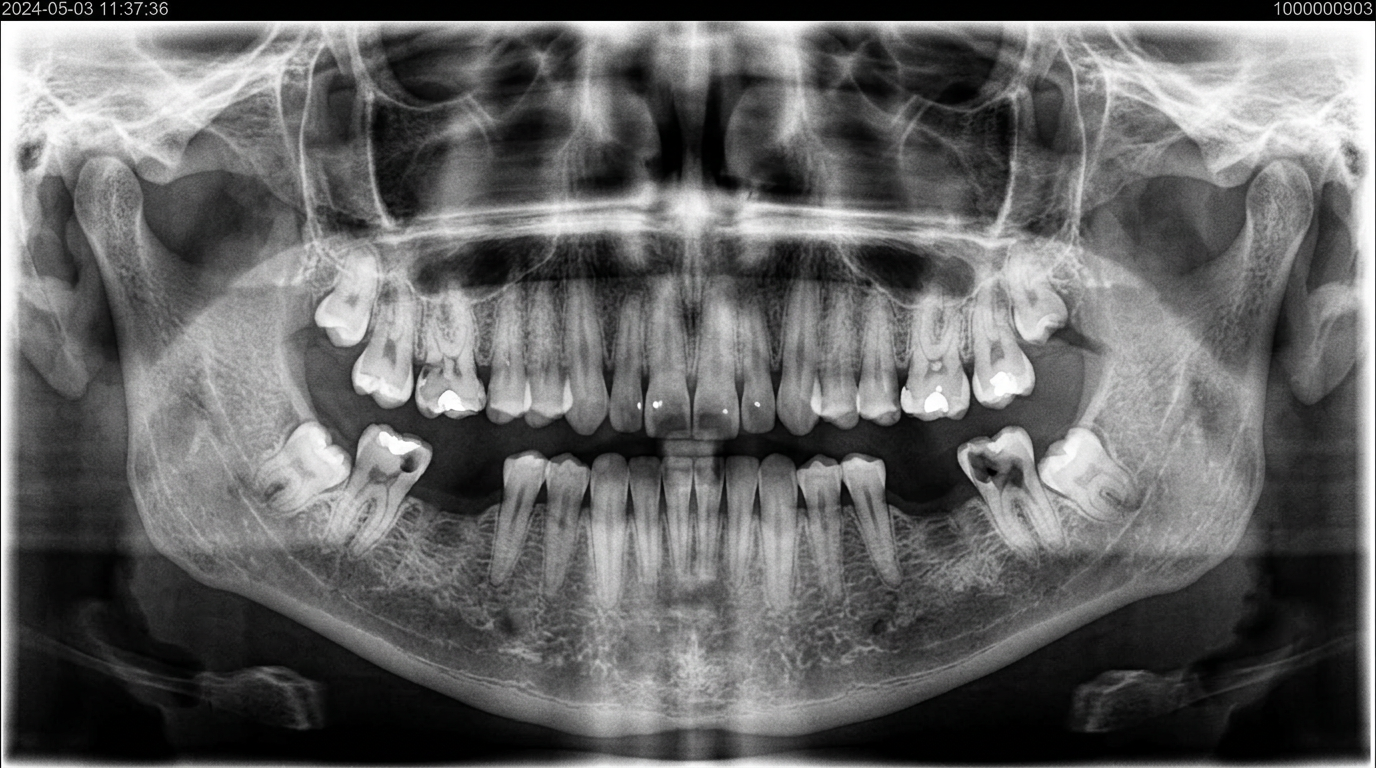

AFTER하악 사랑니 4개 동시 발치 (수평매복 포함) 파노라마 애프터

수평매복 사랑니 4개를 동일 날짜에 안전하게 발치한 케이스입니다.

신경 손상 없이 안전하게 완료되었습니다.